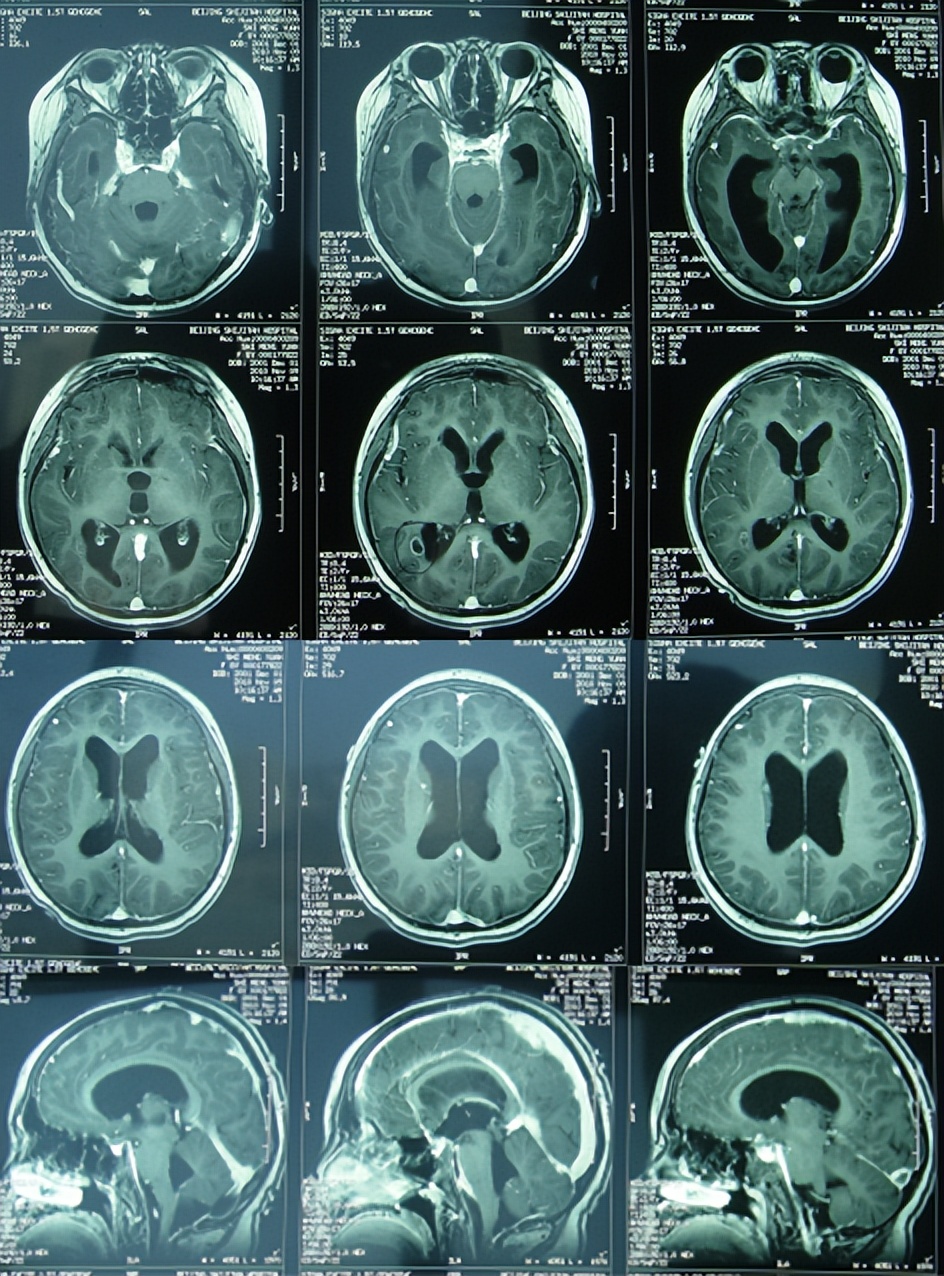

出院后1年零4个月即2012年7月15日复查。复查时:已完全恢复正常健康的状态,激素性面部也完全消失,并向医护人员展示了学习优秀的奖状,也这说明了其智力也完全回到了正常健康水平(图-23);虽此时复查颅脑核磁虽显示第四脑室扩大、感染性小脑扁桃体下疝合并脊髓空洞的异常后遗症表现(图-24);但患儿目前状态一切正常,因此建议继续观察定期复查。

图-24:2012年7月15日头颅核磁